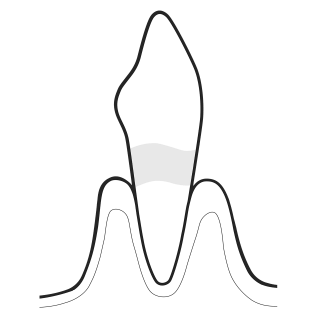

02 DISCLOSE

Make Biofilm visible:

- Highlight to patients the disclosed biofilm and their problematic areas with EMS Biofilm Discloser

- The color will guide biofilm removal

- Once biofilm is removed, calculus is easier to detect